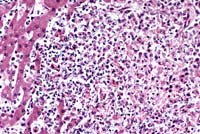

- Case 12-1. Liver. Acute necrosis with intact parenchyma.

10X

- AFIP Diagnoses:

- 1. Liver: Hepatitis, necrotizing, acute, periportal to midzonal,

diffuse, moderate, rabbit, lagomorph.

- 2. Lung: Fibrin thrombi, multifocal, with mild acute interstitial

pneumonia.

- 3. Lung, blood vessels: Medial hypertrophy, multifocal, moderate.

- 4. Spleen: Congestion, hemorrhage, and fibrin deposition,

acute, diffuse, severe, with lymphoid necrosis.

- This case is typical for the disease in susceptible adult

rabbits, and is almost uniformly fatal. Many animals are found

dead without premonitory signs, and those found alive rapidly

become comatose and die quietly. Blood-stained frothy fluid may

exude from external nares, and the lungs are edematous. Typically,

there is complete destruction of the sinusoidal architecture

of the liver and spleen, and replacement by fibrinous coagulum

containing erythrocytes. Destruction of white pulp may occur

as in this case, but is not uniformly present and may be secondary

to stress rather than a direct effect. Acute coagulation necrosis

in the liver is typically periportal, extending to midzonal areas

as in this case, and is usually accompanied by a minimal inflammatory

response.